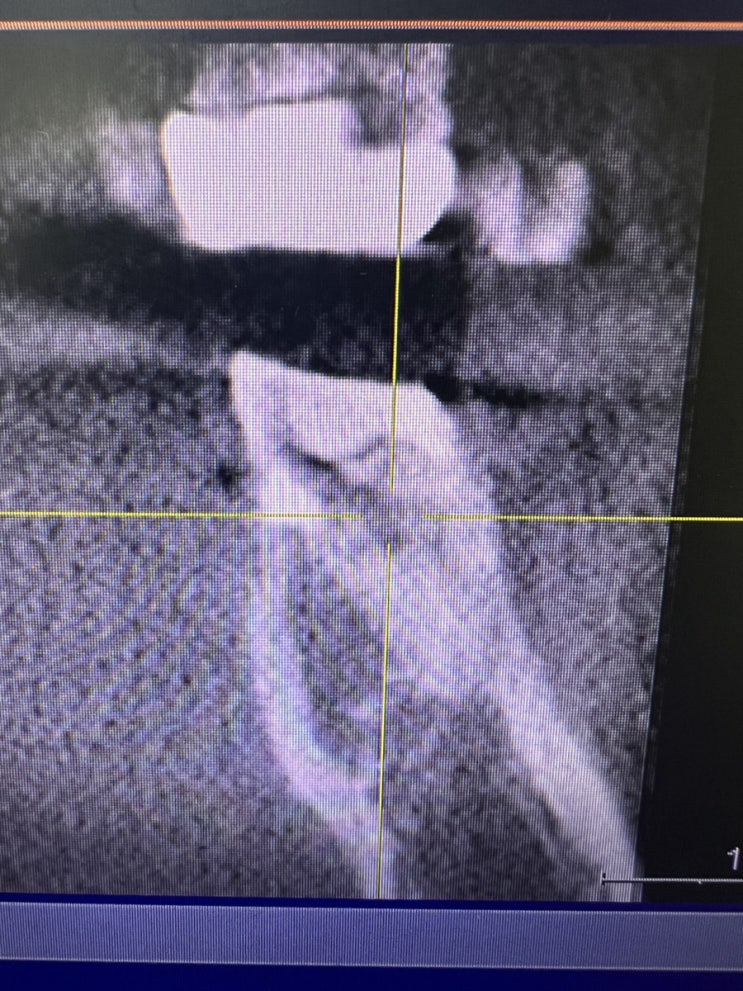

간단한 치과일기] 신경치료 시작할때 치아 각도에 주의하자.

이전에 크게 치료한 치아에 추가적인 충치(우식)이 생겨 신경치료를 시작한 환자. 정상적인 치아의 각도라...